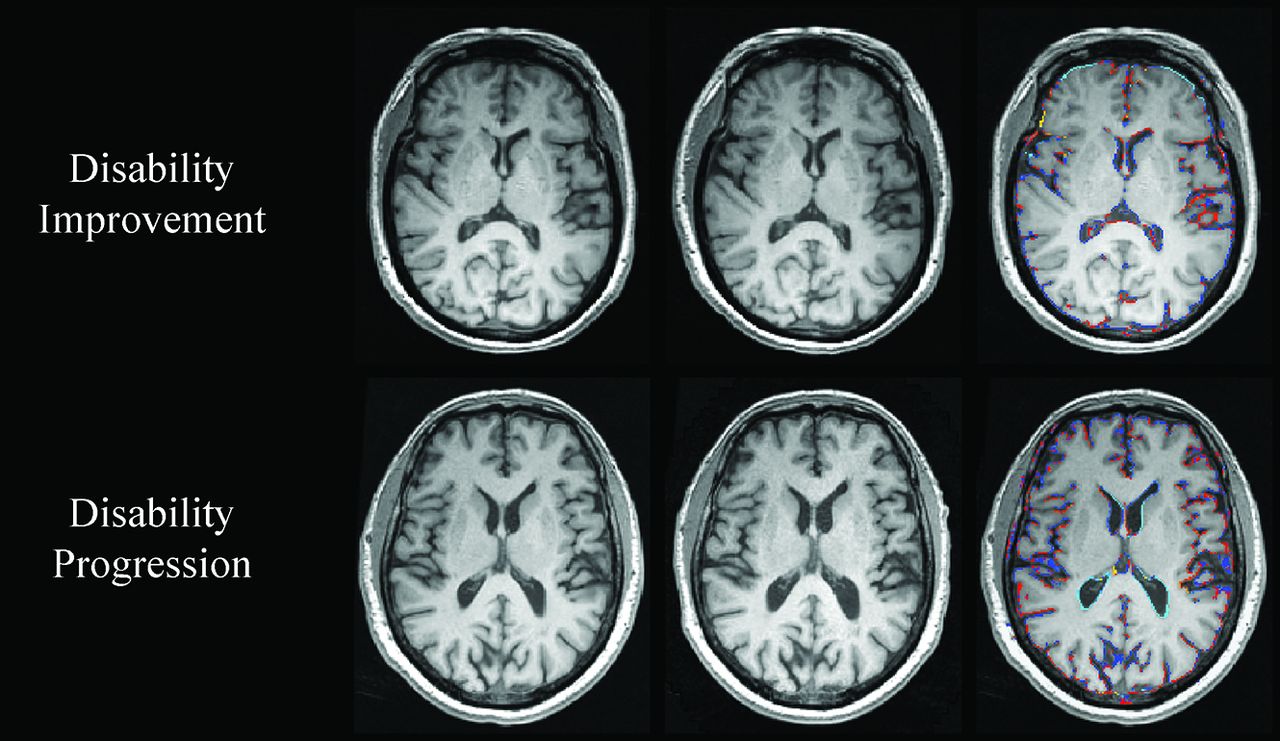

On-line Table 2 shows PLVVC and PBVC in disability progression, disability improvement, and stable groups. Figures 1 and 2 show representative changes of PLVVC and PBVC in disability progression and disability improvement in individual patients during follow-up, respectively. At baseline, there were no significant LVV and whole-brain volume differences among patients with MS in the disability progression, disability improvement, and stable groups.

Change in whole-brain volume in patients with MS with disability improvement and disability progression. In the upper and lower rows are shown patients with MS with disability improvement and disability progression, respectively. From left to right are baseline and follow-up 3D-T1WI, and a SIENA brain volume change edge map showing areas of atrophy (in blue-light blue) and growth (in red-yellow). Please note the higher annualized PBVC rate in disability progressed (−2.4%) compared with disability improved (−0.5%).

The annualized PBVC was −0.7% ± 0.7% in the disability improvement, −0.8% ± 0.7% in stable, and −1.1% ± 1.1% in disability progression groups (adjusted P = .001). The disability improvement group had significantly lower total (adjusted P = .01) and annualized (adjusted P = .02) PBVC compared with the disability progression group. The stable group had significantly lower total (adjusted P < .001) and annualized PBVC compared with the disability progression group (adjusted P = .01). The disability improvement group did not show a significant difference in total (adjusted P = 1.0) or annualized PBVC (adjusted P = 1.0) compared with the stable group. The estimated means and 95% confidence intervals for the analyses are shown in On-line Table 3.